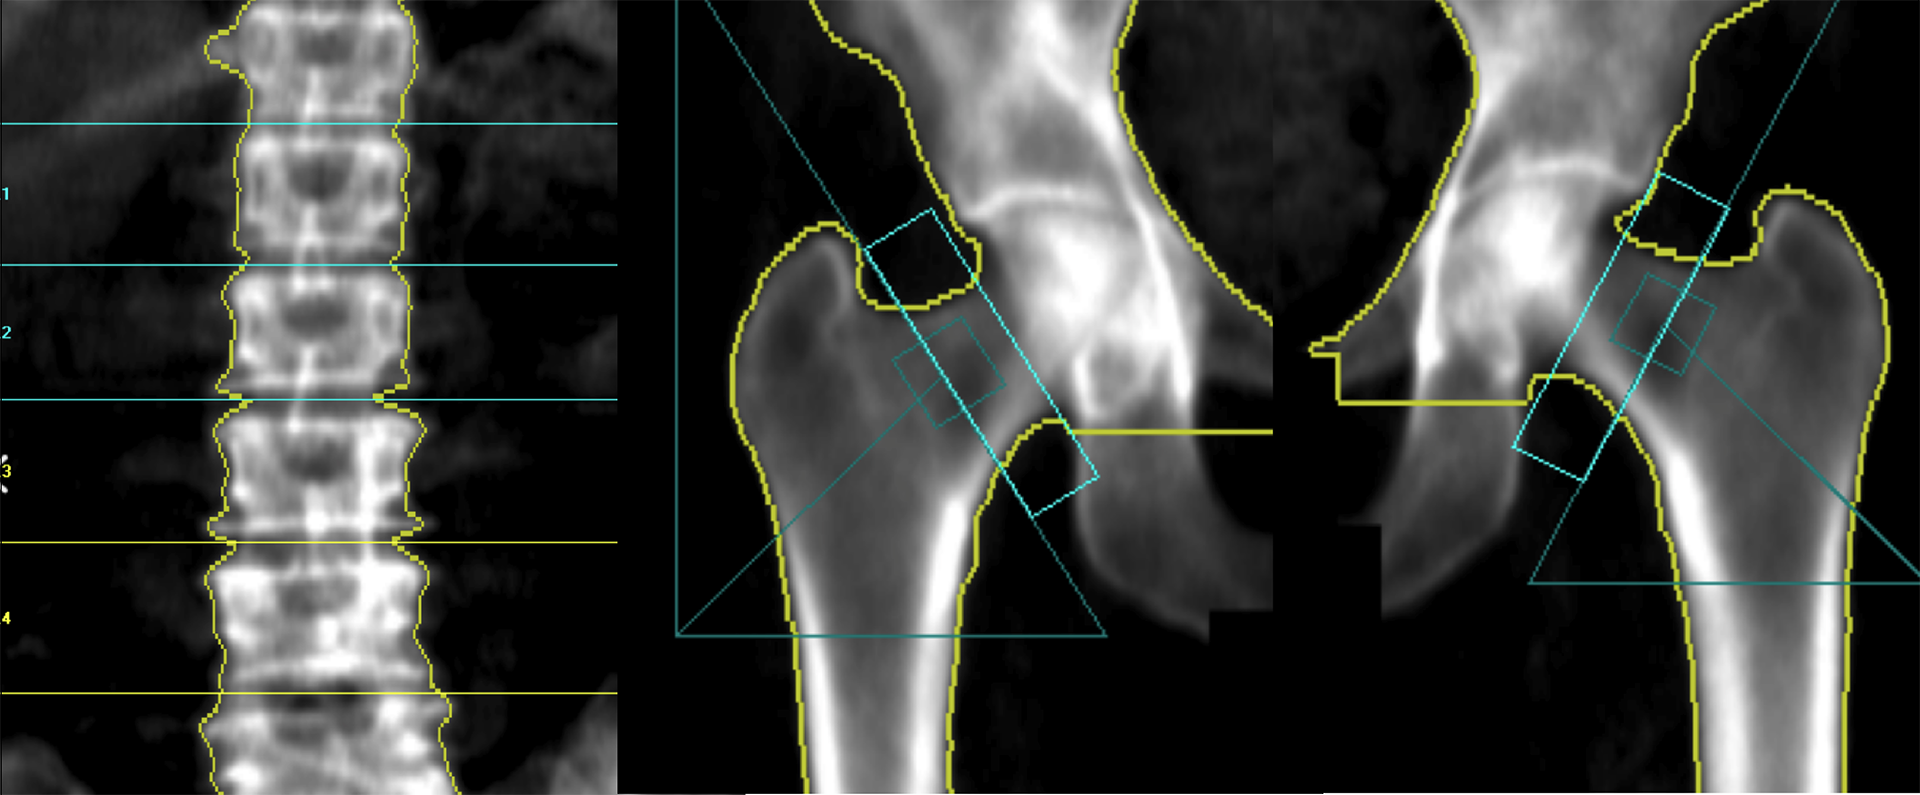

Densitometría Ósea

• Densitometría Ósea Cadera

• Densitometría Ósea Columna